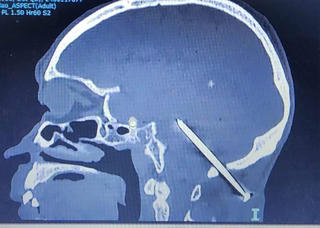

từ khóa: #Đinh đâm xuyên não